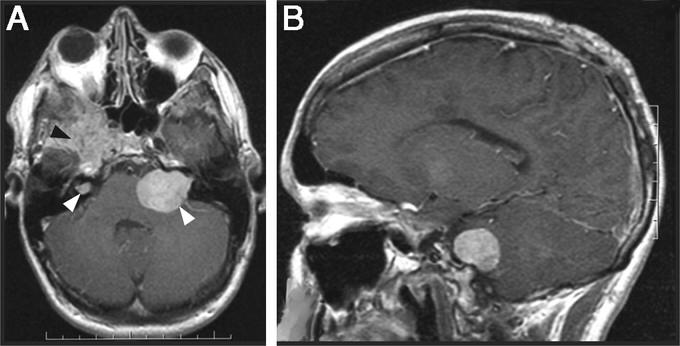

Шваннома при контрастной МРТ